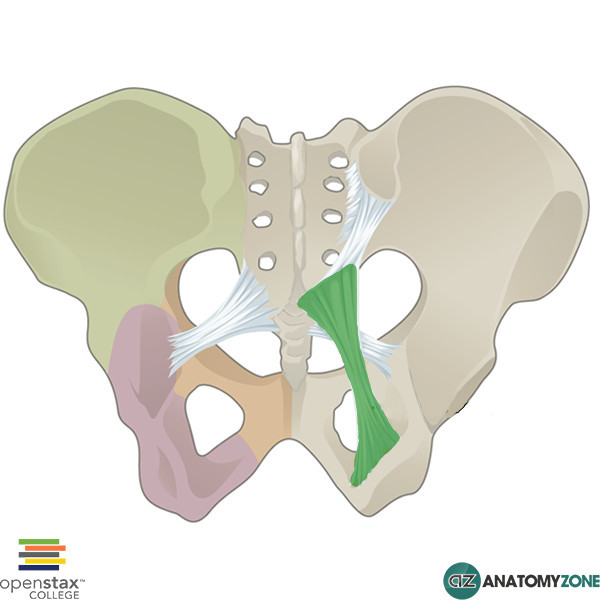

What is this structure?

Sacroiliac ligament

What is this structure?

Sacrotubular ligament

What is this structure?

Sacrospinous ligament